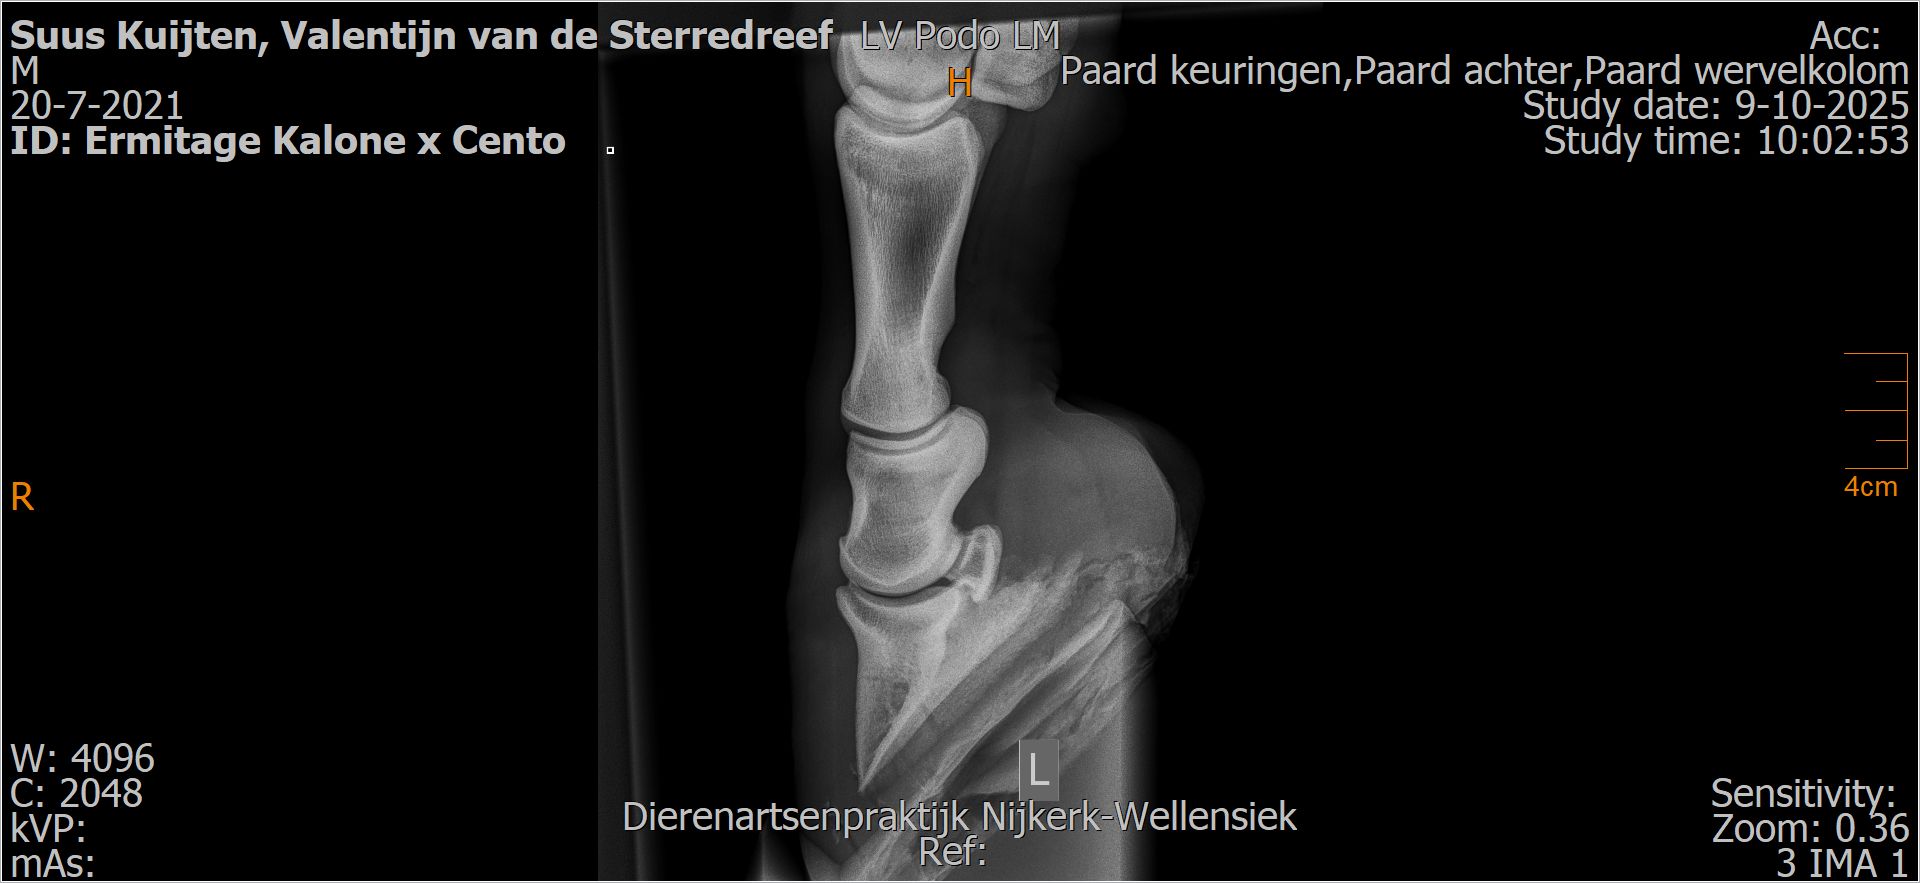

Valentijn van de Sterredreef

Leeftijd:

4

Röntgenfoto’s